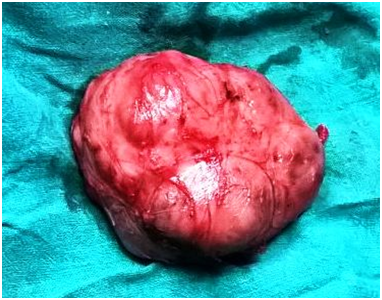

Paragangliomas can develop anywhere along the midline of the retroperitoneum. The exact incidence of retroperitoneal paragangliomas is unknown, although males are typically affected more frequently than Females. In addition, most patients are diagnosed between 30 and 45years of age.1 Clinically, patients with a retroperitoneal paraganglioma often present with back pain or a palpable mass.2 Conventional treatment for paragangliomas typically involves complete surgical excision, while surgical debulking is considered a mainstay of palliative therapy for malignant paragangliomas. In some cases, complete excision is difficult due to the highly vascular nature of paragangliomas and their proximity to major blood vessels (Figure 1-4).

Figure 1 Gross specimen of excised tumor.

Figure 3 Excised tumor.